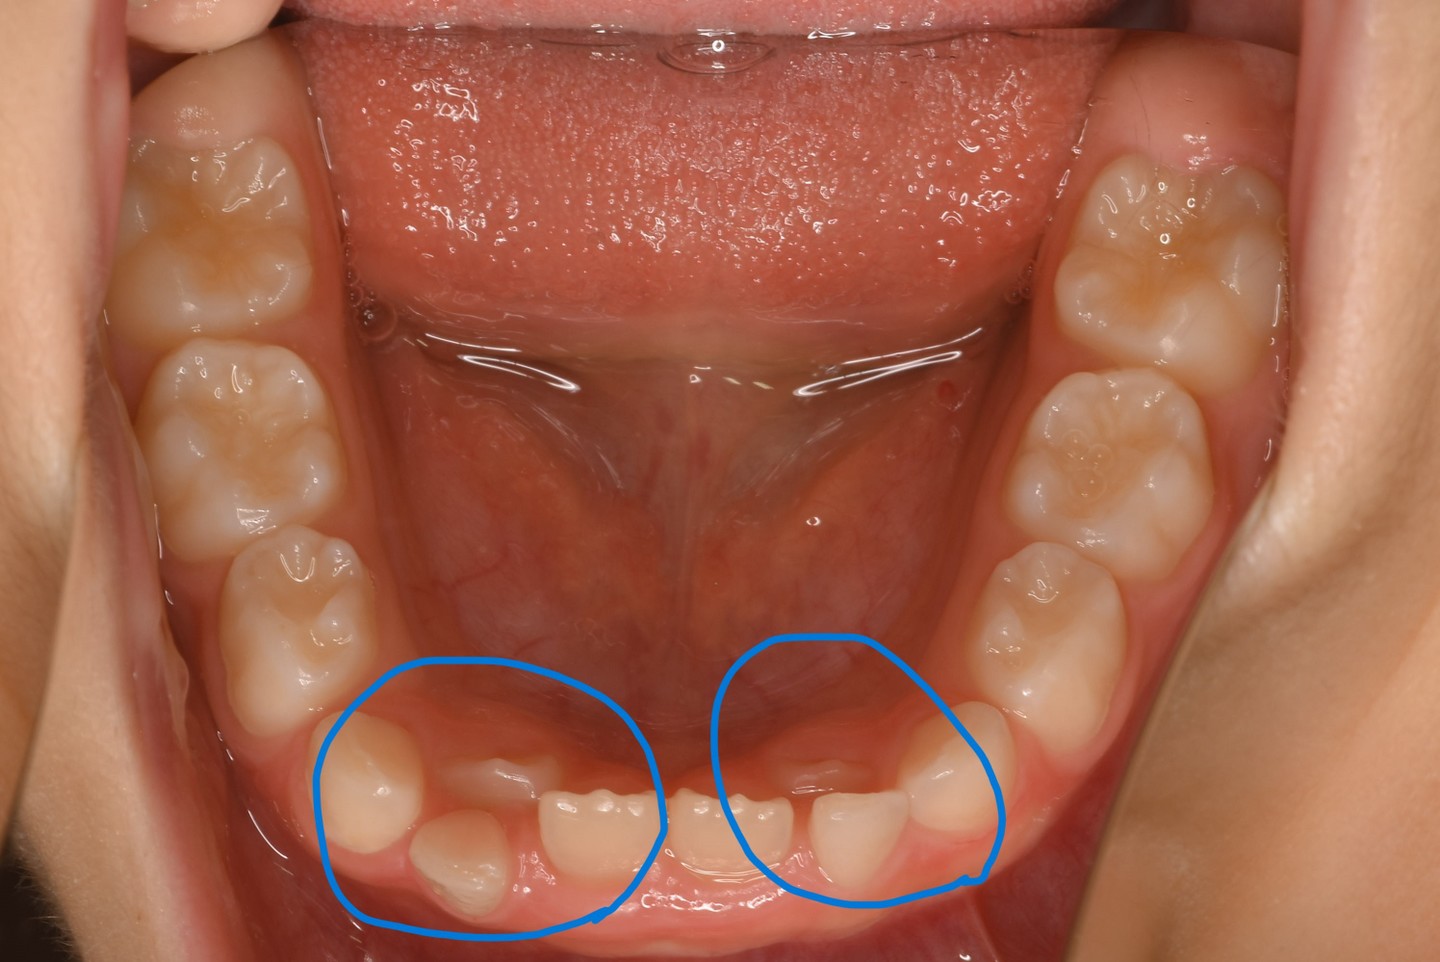

乳歯が抜けない内に生えて来たときの画像

お子さんの乳歯が抜けないうちに永久歯が生えてきたとき、歯医者さんにみてもらおう!と親御さんが連れて来てくださいます。